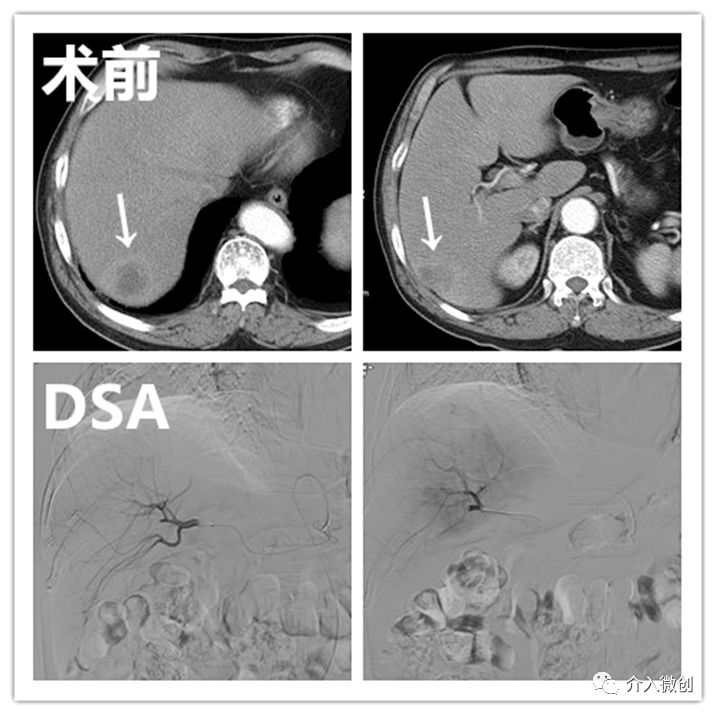

病例1

老年男性,诊断为右肺癌并纵隔淋巴结、肝多发转移。活检病理示:大细胞性未分化癌。肺部病灶经姑息性放化疗后有所控制,但肝脏病灶出现进展,遂行载药微球栓塞治疗。

肝动脉化疗栓塞治疗